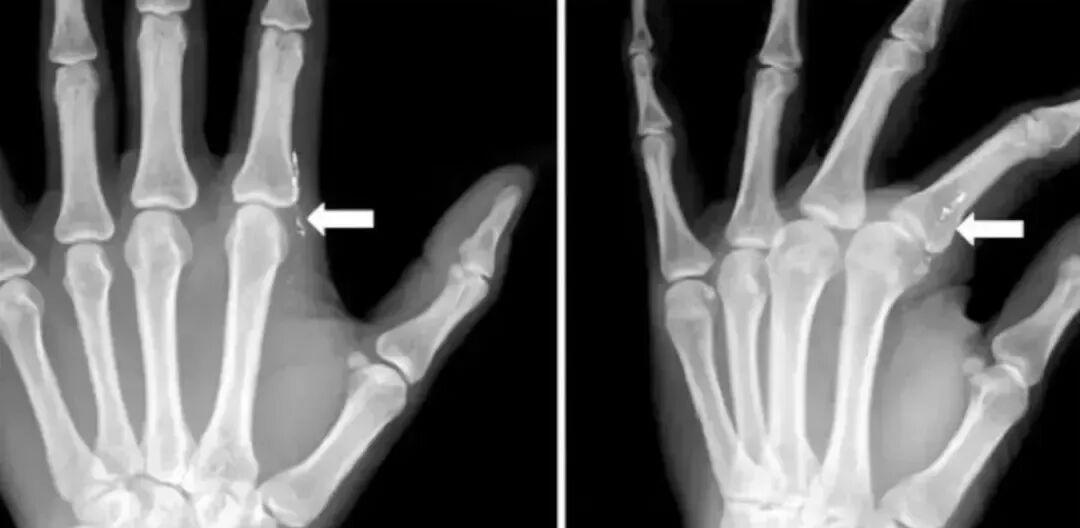

J Hand Surg Asian Pac 曾發表過這樣一個病例[1]:一名 42 歲的媽媽去看病,覺得「左食指有異物感」。

醫生追問病史瞭解到,她在 1 個月前在給女兒量體溫時,不小心打碎水銀溫度計。清理體溫計碎片的時候,左手指被刺傷,當時覺得沒有大礙,就沒有就診。

醫生髮現,患者左手手指有肉芽組織,檢驗血液、尿液後發現,有汞中毒的跡象。

左食指第二掌趾關節橈側疼痛

圖片來源:文獻[1]

X 片可見皮下線狀高密度影